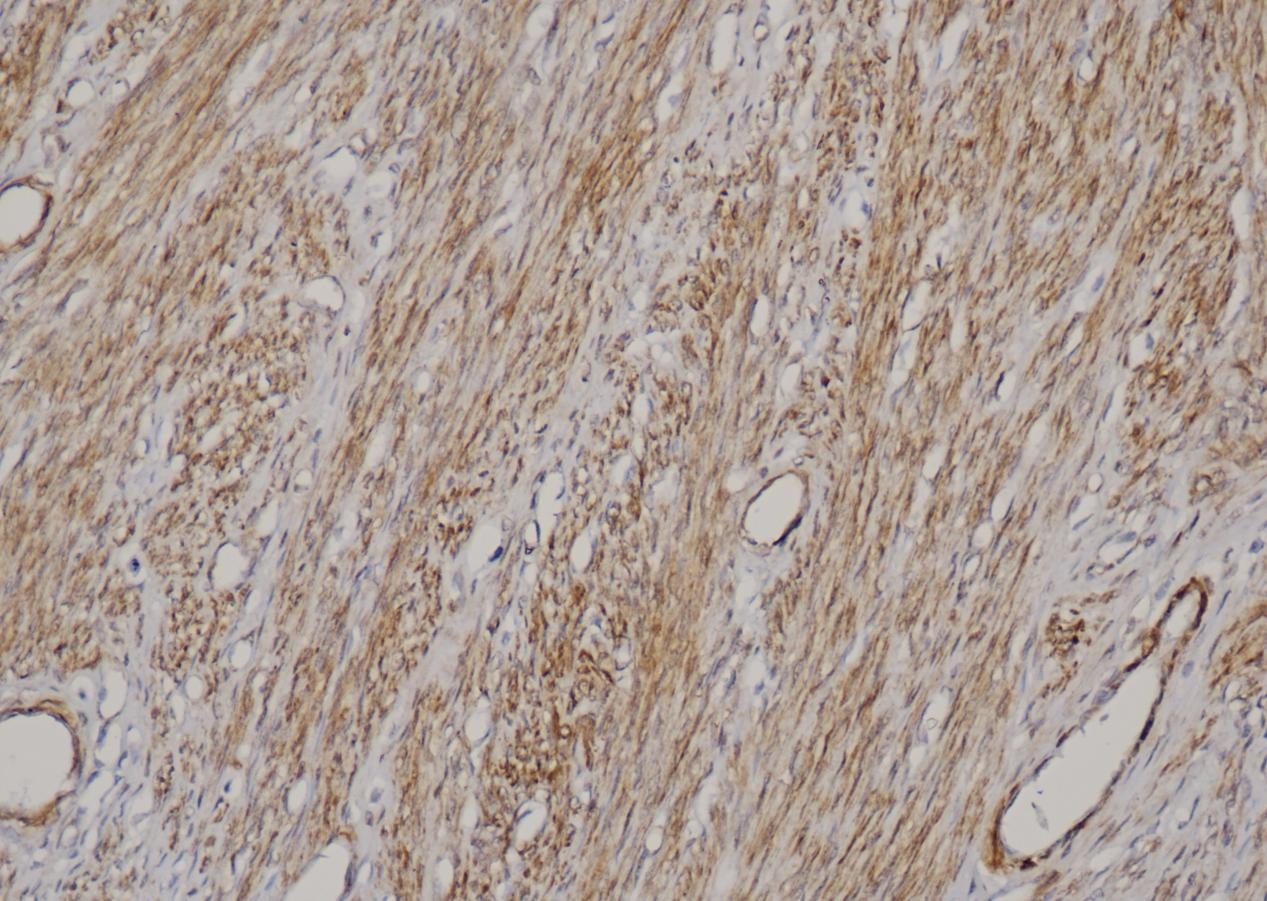

Caldesmon

Caldesmon (钙调蛋白结合蛋白)是一种平滑肌肌动蛋白和钙调节蛋白的结合蛋白,位于细肌丝,调节 肌动蛋白和肌球蛋白的相互作用,主要存在于平滑肌细胞。Caldesmon 可用于正常平滑肌细胞及其肿瘤的标记,真性平滑肌肿瘤与肌纤维母细胞瘤、卵巢/腹膜浆液性乳头状癌与上皮样间皮瘤的鉴别,与CD10 联用 可用于子宫内膜间质肉瘤与子宫平滑肌肿瘤的鉴别诊断。